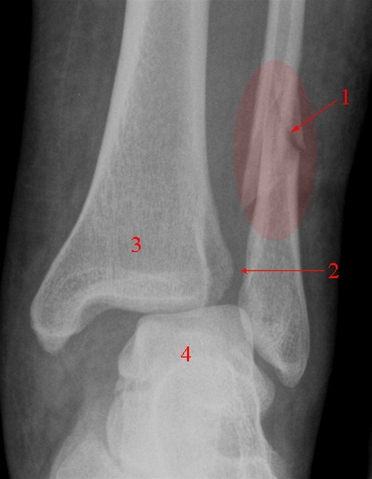

På røntgenbilledet nedenfor er bruddet på anklen markeret med nummer 1, og ses under den røde farve.

Brud på ankel